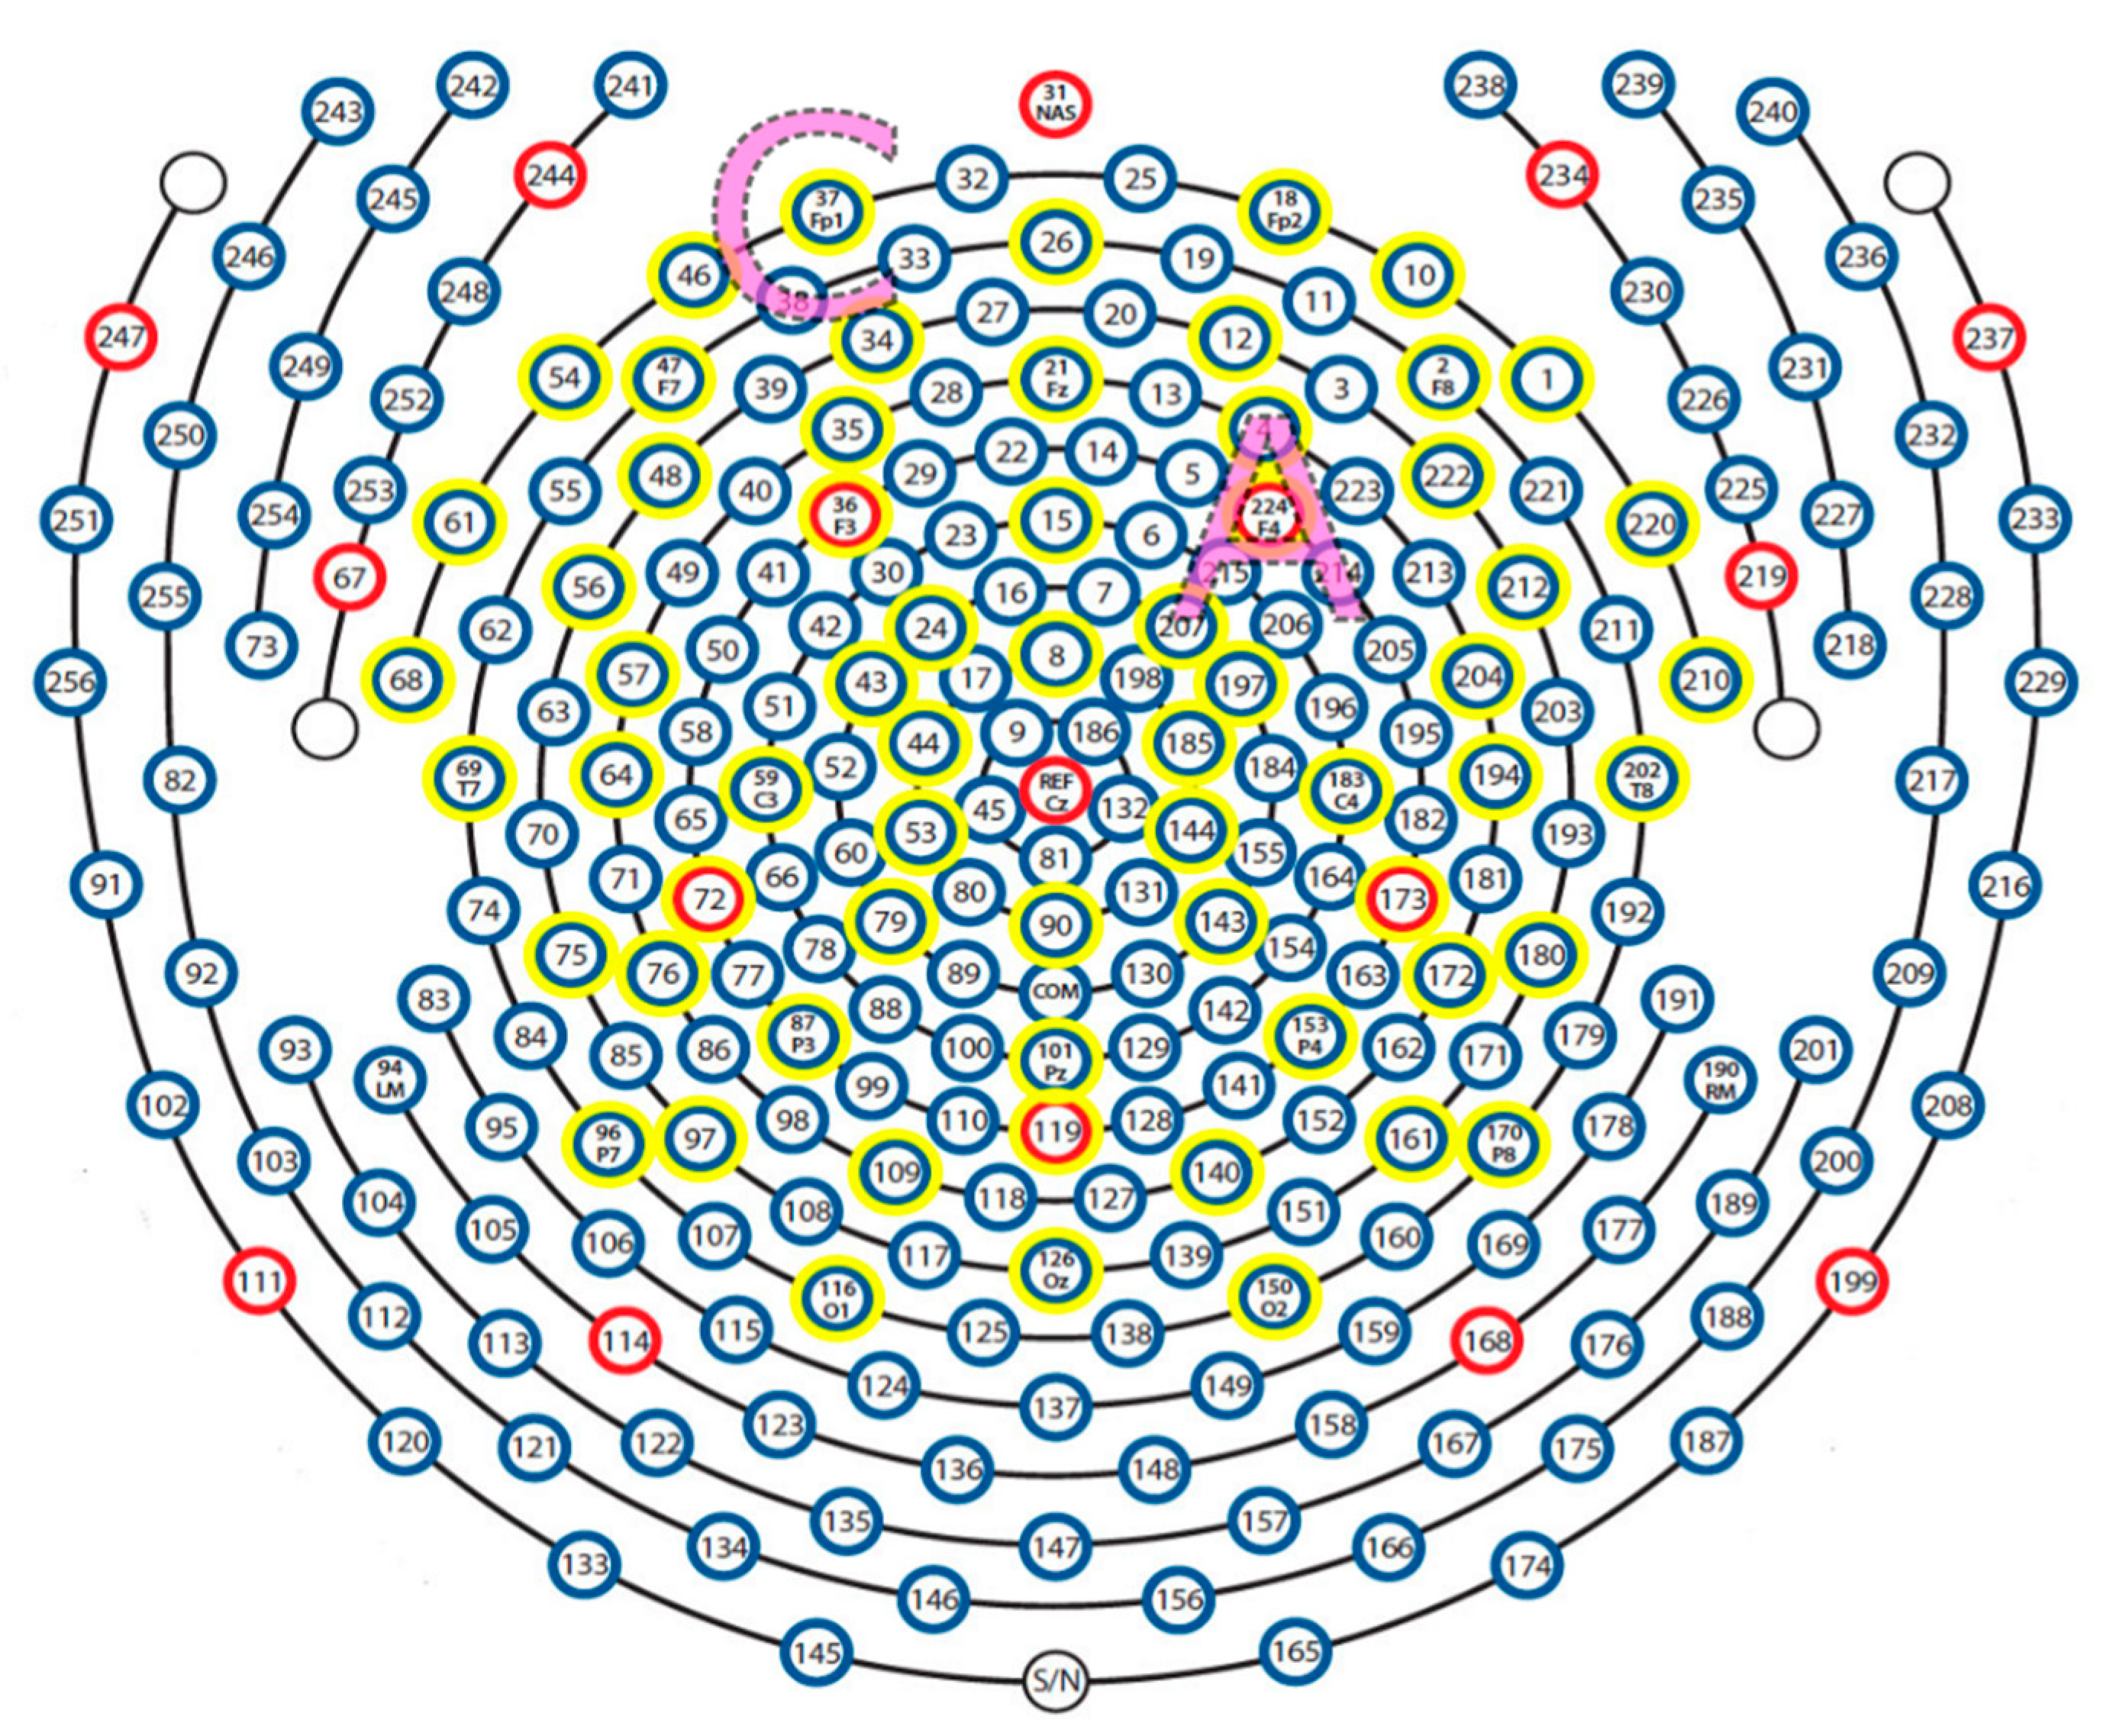

2.4. EEG Recording and Analysis